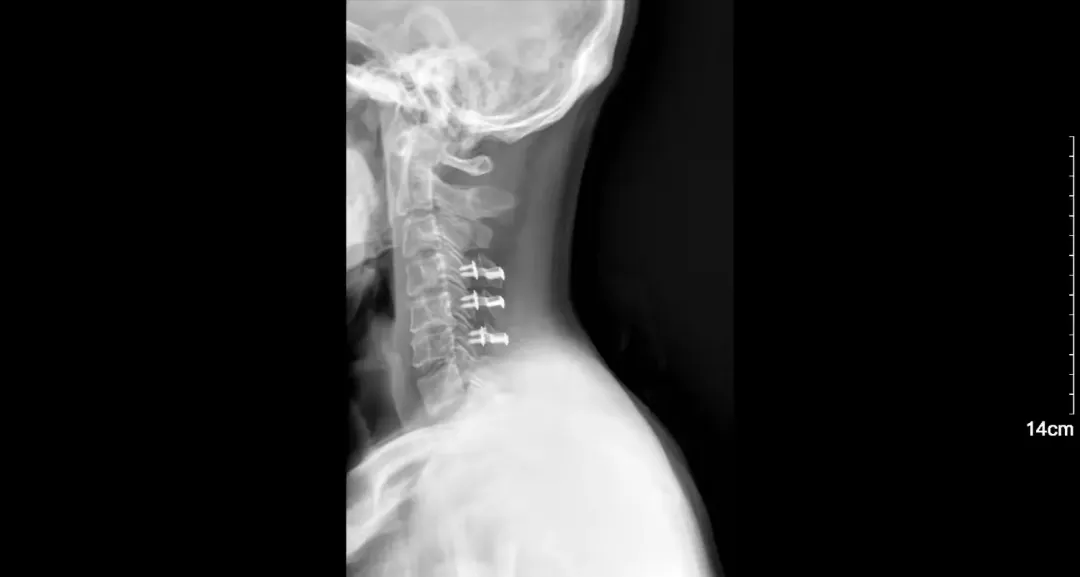

「手术禁区」市五院骨科勇闯男子车祸险瘫痪

车祸致第二颈椎骨折,精湛医术救治助其平安脱险